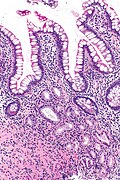

Micrograph showing pseudopyloric mucous glands (bottom) and intestinal epithelium (top). H&E stain.

Pseudopyloric mucous glands, also pyloric gland metaplasia,[1] is a change seen the intestine. It is associated with Crohn's disease.

• Round glands composed of tall columnar cells with:

• Abundant pale (pink) cytoplasm.

• Small basal nuclei.

• Usually in the deep aspect of the mucosa.

• The lining cells look somewhat like stubby champagne flutes.